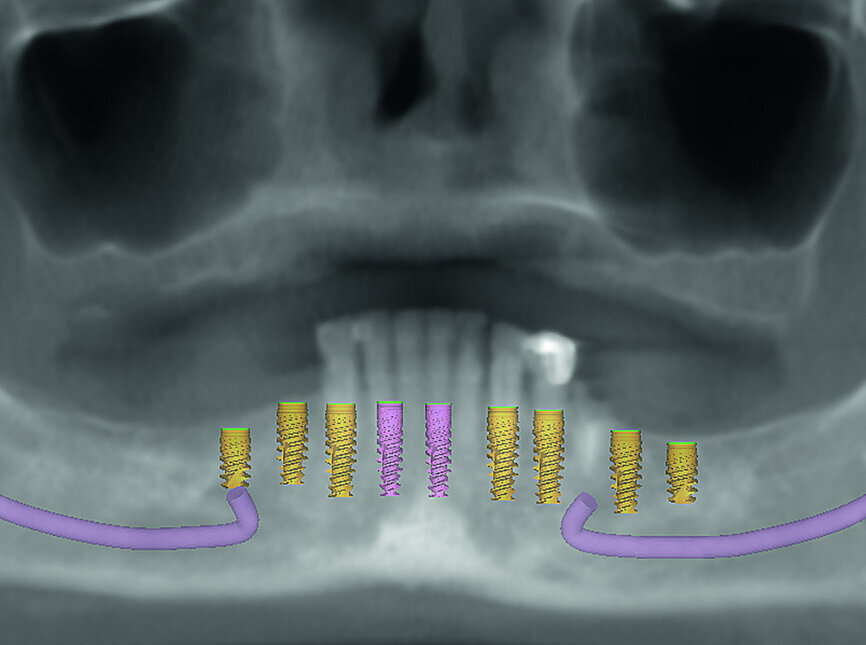

La patiente est revenue pour passer la visite des enregistrements. Au cours de celle-ci, des empreintes maxillaires et mandibulaires ont été prises afin de fabriquer des prothèses provisoires immédiates qui seraient mises en place lors de la visite prévue pour la chirurgie. Le scanner CS 8100 3D (Carestream Dental) a été utilisé pour acquérir des images CBCT, et obtenir ainsi les données nécessaires au plan de traitement virtuel. Les données 3D acquises grâce à la numérisation CBCT ont permis de déterminer les paramètres idéaux de longueur, de largeur et de positionnement des implants, aux endroits clés des arcades édentées de la patiente, soit les régions des premières molaires, premières prémolaires, canines et incisives centrales (Figs. 3–6). Des guides chirurgicaux à appui osseux maxillaire et mandibulaire ont été produits d’après le plan de traitement numérique conçu par 3D Diagnostix (Figs. 7 et 8).

Fig 3 Présentation du traitement de l’arcade maxillaire

Fig 4 Présentation du traitement de l’arcade mandibulaire

Fig 5 Analyse dento-faciale du traitement implantaire proposé dans l’arcade maxillaire

Fig 6 Analyse dento-faciale du traitement implantaire proposé dans l’arcade mandibulaire